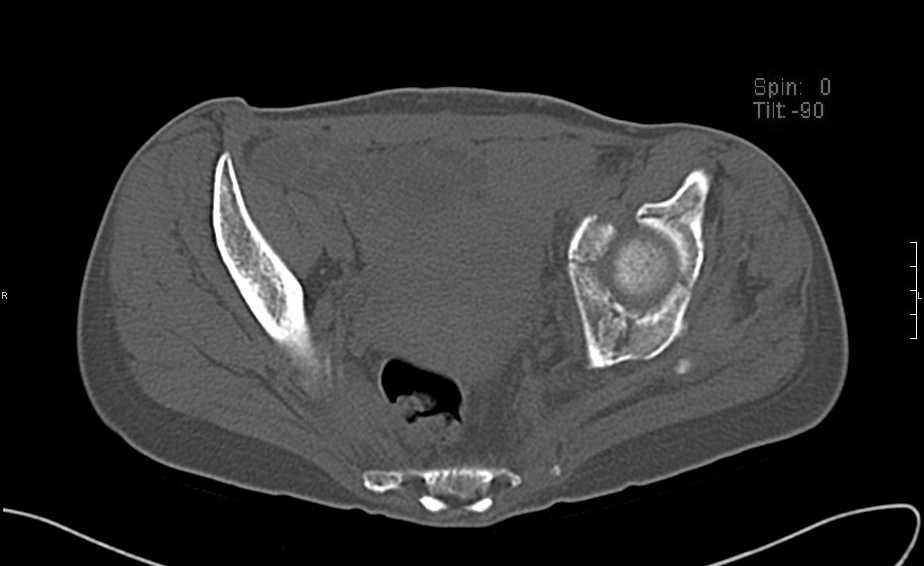

Больная 43 года (промышленный альпинист), 28.07.08 в результате падения с 5 этажа получила политравму: Перелом свода и основания черепа. Вертикально-нестабильное повреждение таза, осложнённое разрывом мочевого пузыря. Чрезвертельный перелом левого бедра. Перелом правой таранной кости, переломовывих правой кубовидной кости. Тупая травма живота, разрыв печени, ушиб почек. Забрюшинная гематома. В день травмы - лапаротомия, ушивание ран печени. Разрыв мочевого пузыря не диагностирован. Течение болезни осложнилось развитием мочевого затёка и обширной пред- и забрюшинной флегмоны, сформировался свищ мочевого пузыря. 19.8.2008 вскрытие, дренировние флегмоны, ревизия мочевого пузыря, обтурация мочевого свища (свищ закрылся в октябре), 1.10.2008 некрэктомия, пластика по Шеде-Лидскому правой кубовидной кости. По результатам КТ диагностирован рак правой почки (диагностическая находка), 8.10.2008 нефрэктомия справа. Переломы велись консервативно. Имеется вертикальное смещение левой половины таза с выраженным отведением крыла (клинически подвижности нет), несросшийся низкий двухколонный перелом левой вертлужной впадины с потерей конгруэнтности, укорочение около5 см, застарелый разрыв лонного сочленения, неправильно сросшиеся переломы обеих ветвей правой лонной кости с укорочением, патологическая подвижность лоно-седалищного фрагмента слева. Правая нижняя конечность неопорна, несмотря на то, что лежа прямую ногу поднимает, ходит на левой ноге (ортопедическая обувь) с костылями, справа тазобедренный ортез. Седалищные нервы работают.Урологи отпустили больную на 6 мес.